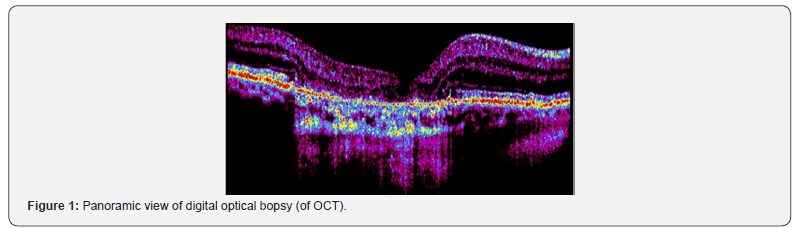

The cellular and tissue images, although they have a known pattern, show the difference of a pure, active image, captured by a tomography (OCT), or optical coherence tomography. Information generates “every being-every particle, every force field, even the time-space continuum.” This is another way of probing the paradox of the observer: the result of an experiment is affected, even determined, when it is observed. Not only is the observer watching, he is asking questions and utterances that ultimately must be expressed as discrete bits. “What we call reality,” Wheeler timidly wrote, “arises in the last analysis of posing yes or no questions.” “All physical thing in order to transform the numeric information that a pixel stores in a color, we must know, in addition to the depth and brightness of the color (the size in bits of the pixel), the color model we are using. For example, the RGB (Red-Green-Blue) color model allows you to create a color by making two basic colors and one secondary color: red and blue (primary) and green (secondary). In this way, depending on the amount of each of them that we use we will see one result or another. For example, the violet color is obtained by mixing red and blue.

Einstein suggested in his theories, the existence of a field holding space-time transformations and mass - energy. This field is the pixel. In the different photos that we show, can be seen digital secuentiation of the retina tissue, detection technique based in sequencing images, obtained in our Digital Laboratory (Maimonides University) (Figure 1-4).